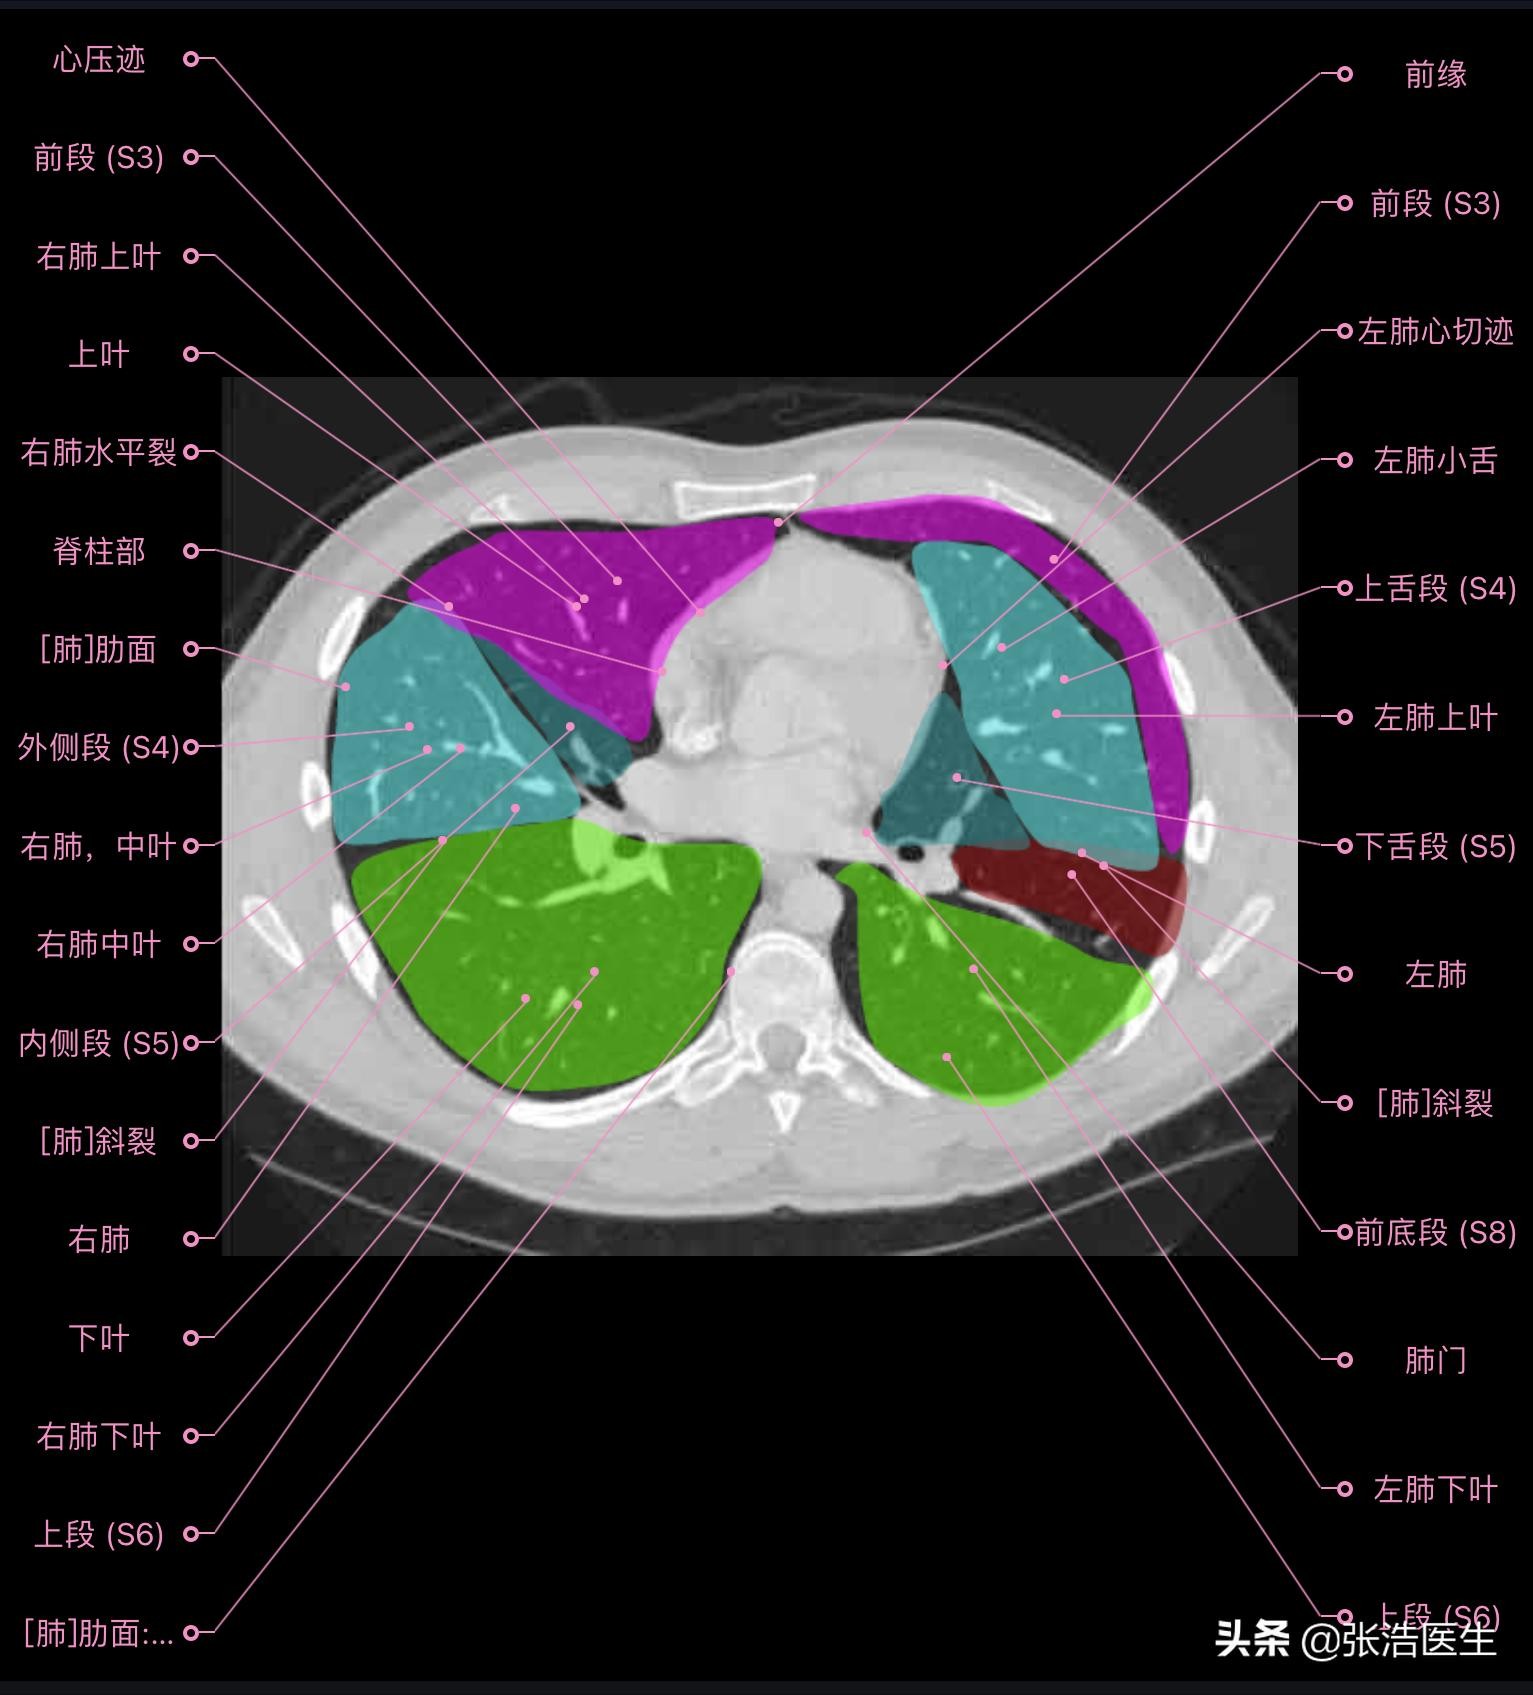

肺部CT横断面高清解剖图谱(图层2)

肺部CT横断面 高清解剖图谱

精选15层常用解剖断面

每一层都带有详细标注,值得收藏学习!